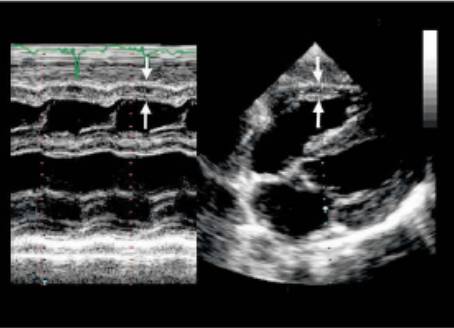

直接二维测量或在二维引导下的M-型曲线上测量。

图|胸骨旁左心长轴切面,二尖瓣瓣尖水平。左图为舒张末期,右图为收缩末期。

随着图像处理技术的改进,已经提高心脏结构的分辨率。可按照真实的组织和血流的界面来测量室间隔和左心室后壁的厚度,而不是像以前测量前缘回声之间的距离。

ASE推荐于二尖瓣瓣尖水平胸骨旁短轴切面直接测量或采用M型曲线测量。M-型超声时间分辨率好。有助于帮助二维超声区分临近左室后壁的肌小梁、室间隔左室面的假腱索、室间隔右室面的调节束等结构。即使采用二维引导也可能无法保证M-型取样线完全垂直于室间隔和左心室后壁。